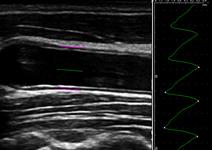

The condition of atherosclerosis in the carotid arteries can be analyzed based on ultrasound imaging with the clinical application package (CAP) M’Ath. For the detection of early atherosclerosis the automated IMT (Intima Media Thickness) and distensibility measurement provides important results. Semiautomatic plaque and stenosis measurements support the diagnosis in advanced stages of atherosclerosis.

The M’Ath CAP is well validated with more than 10,000 patients and offers reliable results. Additionally the user can work with different ultrasound systems and is not limited to specific vendors to perform all the measurements of this analysis tool.